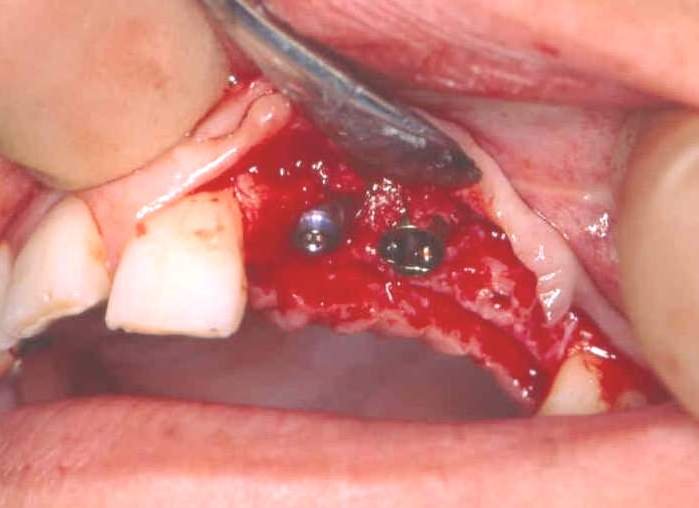

It is essential to avoid contamination of the pure titanium surface of the implant with stainless steel instruments or soft tissue. The implant is screwed into the bone at slow speed until the maximum torque is reached. Over-tightening can strip the implant from the bone. Sometimes exposed threads are seen on the buccal/labial aspect of the implant on final placement. If there is primary stability, the majority of implants will integrate despite exposed threads (Figure 8).

Figure 8: Implant socket preparation.

These threads can also be covered by bone harvested by a surgical filter or bone substitute. Semipermeable membrane covering this can promote healing by guided tissue regeneration (Figure 9). A cover screw is fitted over the internal threads of the implant (Figure 10) and the wound closed. The patient is advised not to wear their prosthesis for 7 to 10 days, followed by occasional wear only.

Figure 9: Material used for guided tissue regeneration.

Figure 10: Dental implants in place with cover screws visible.